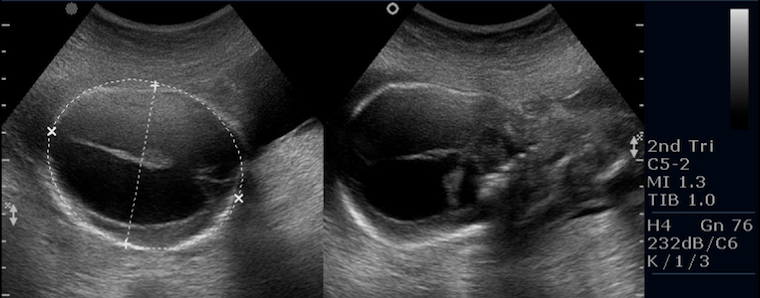

Захворювання можливо діагностувати у плода під час передпологового ультразвукового дослідження. У дитинстві діагностується при регулярному вимірюванні розмірів голови.